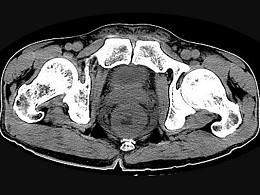

问题 男,56岁,排便形状改变,便不尽感,CT检查如图所示,下列说法正确的是 ( )

选项 A、此为直肠息肉 B、此为直肠癌 C、其表面光滑,边界清楚 D、肠腔未见狭窄 E、肠壁上有蒂状新生物 单选题

答案 B